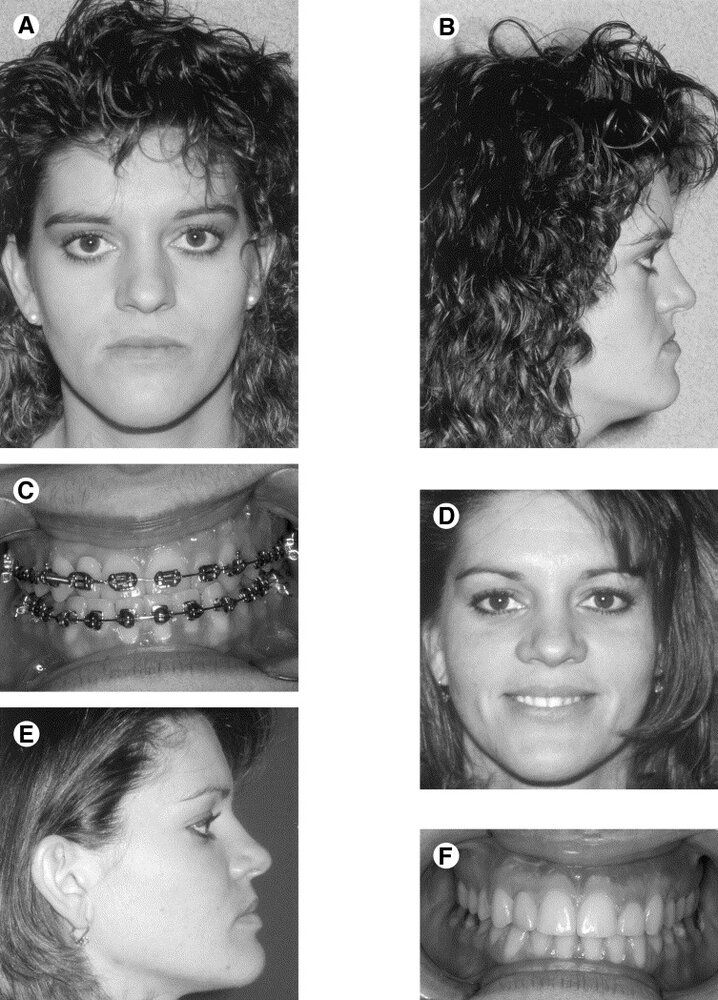

It moves cheekbones upward, give so much under eye support and even change orbital shape. Also widen face and change gonial angle. Is it modified lefort 3?